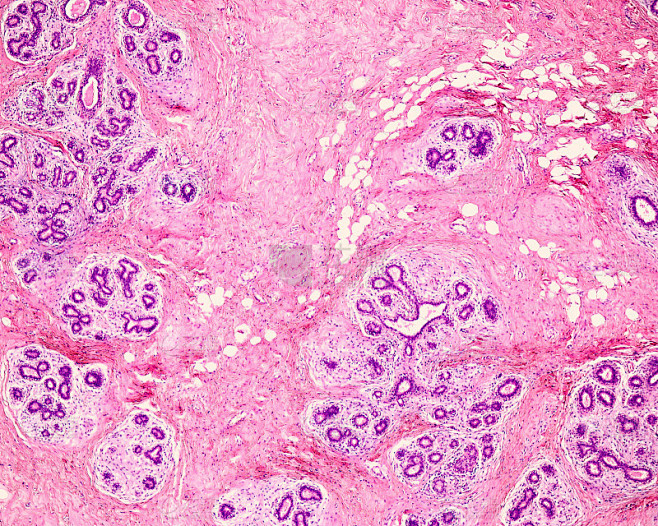

胸腺小体(きょうせんしょうたい、英:Hassall's body)とは胸腺髄質において胸腺細網細胞(胸腺上皮細胞)が同心円状に配列した領域。ハッサル小体とも呼ばれる。胸腺小体は30~100μm程度の大きさであり、中心には1個あるいは数個の変性度の高い大型細胞が位置する。